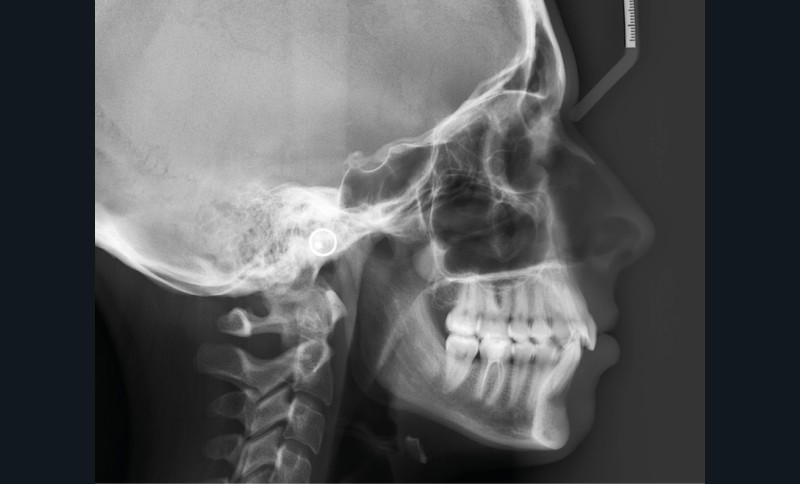

Examens complémentaires (fig. 3a,b)

À la radiographie panoramique, 31 présente une importante image apicale, confirmée par une radiographie rétroalvéolaire et également visible sur la téléradiographie de profil.

Cette dernière montre un schéma squelettique de Classe I et une typologie verticale normodivergente. Les rapports incisifs sont normaux et l’épaisseur des tissus mentonniers est insuffisante pour obtenir la fermeture buccale sans contraction. La symphyse est fine et l’incisive est centrée sur celle-ci.